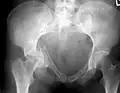

Рентгеновский снимок перелома правой тазовой кости с повреждением вертлужной впадины суставной головкой бедренной кости